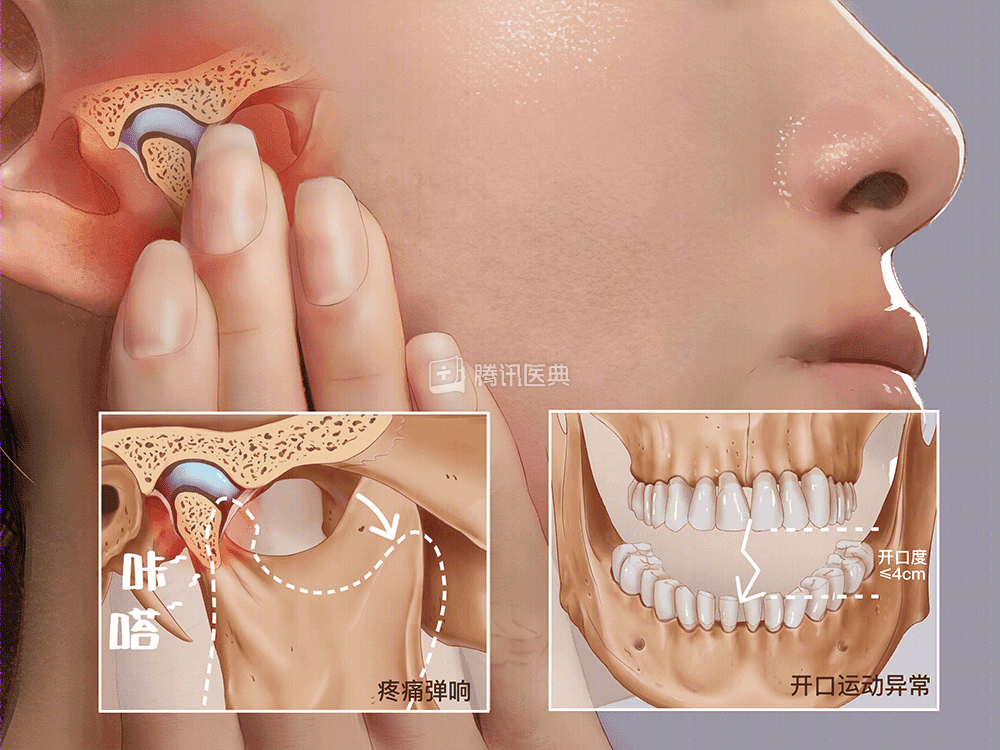

TMD(Temporomandibular Disorders)

颞(niè )下颌关节紊乱病

经医生检查,发现刘女士的张口度仅有13mm,左侧的颞肌、咬肌、耳后有明显压痛,下颌运动受限,经临床和影像检查后,诊断刘女士患有颞下颌关节紊乱病。

「颞下颌关节紊乱病」是口腔颌面部的常见病和多发病之一,人群好发率高达20%-60%,主要表现为颞下颌关节区的疼痛、弹响和张口受限。张口受限时,颞下颌关节的活动性会明显下降,严重时甚至会影响患者的心理状态和生活质量。